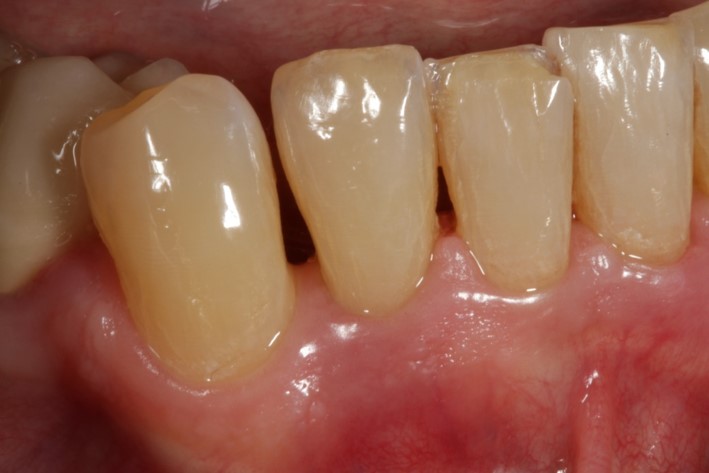

01/08 - Pre-operative clinical situation.

Non-contained intrabony defect treated using Straumann® Emdogain® and a synthetic bone grafting material - Prof. Dr. Dr. A. Kasaj